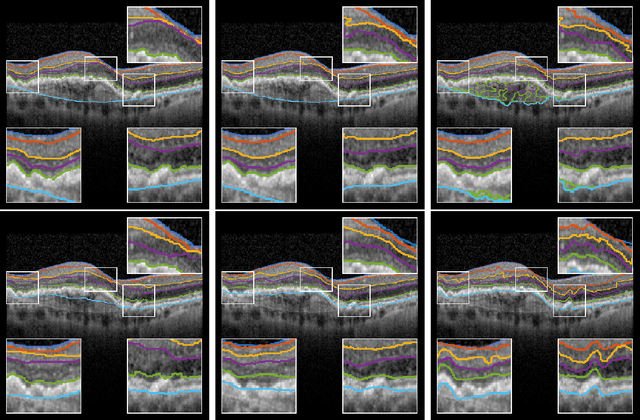

Abstract:The automatic segmentation of retinal layer structures enables clinically-relevant quantification and monitoring of eye disorders over time in OCT imaging. Eyes with late-stage diseases are particularly challenging to segment, as their shape is highly warped due to pathological biomarkers. In this context, we propose a novel fully Convolutional Neural Network (CNN) architecture which combines dilated residual blocks in an asymmetric U-shape configuration, and can segment multiple layers of highly pathological eyes in one shot. We validate our approach on a dataset of late-stage AMD patients and demonstrate lower computational costs and higher performance compared to other state-of-the-art methods.